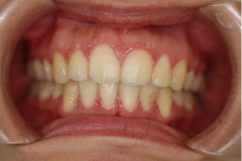

症例名

外科矯正

治療前

治療後

| 主訴 | 受け口、顎が歪んでいる |

|---|---|

| 診断名 | 下顎左側偏位を伴う骨格性下顎前突 |

| 初診時年齢 | 25歳9か月 |

| 主な治療装置 | マルチブラケット装置 |

| 抜歯部位 | 非抜歯 |

| 治療期間 | 2年2か月 |

| 治療費 | 保険診療自己負担額(3割負担)で、¥250,000〜¥300,000 ※外科手術費(保険)は別途(提携病院実施) |

| リスク・副作用 | 矯正中は、口腔を清潔に保たないと、虫歯、歯肉炎、歯周病になるリスクがあります。マルチブラケット装置の使用には、口腔内の刷掃や治療協力が必要です。成人では、強い歯ブラシ圧によって歯肉退縮が起こることがあるので注意して下さい。外科矯正治療は顎位が手術日に変わりますので、事前の舌訓練、嚥下練習が必要です。治療後の保定を怠ると、このような症例では、後戻りが容易に起こるので長期管理が必要です。 |